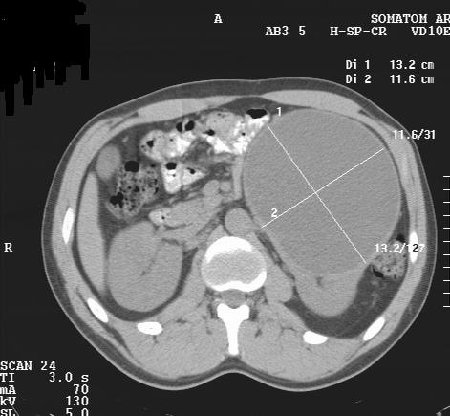

М. 37 лет, жалоб нет, амб. приём, причина назначения УЗИ ОБП: СОЭ 42мм

б\б и м\э консист., как говорится.   Исходит из н\ полюса левой почки

Вложения

2.JPG

3.JPG

4.JPG

КТ сделали без контрастирования, смысл такого КТ??? Диагностической ценности-ноль.